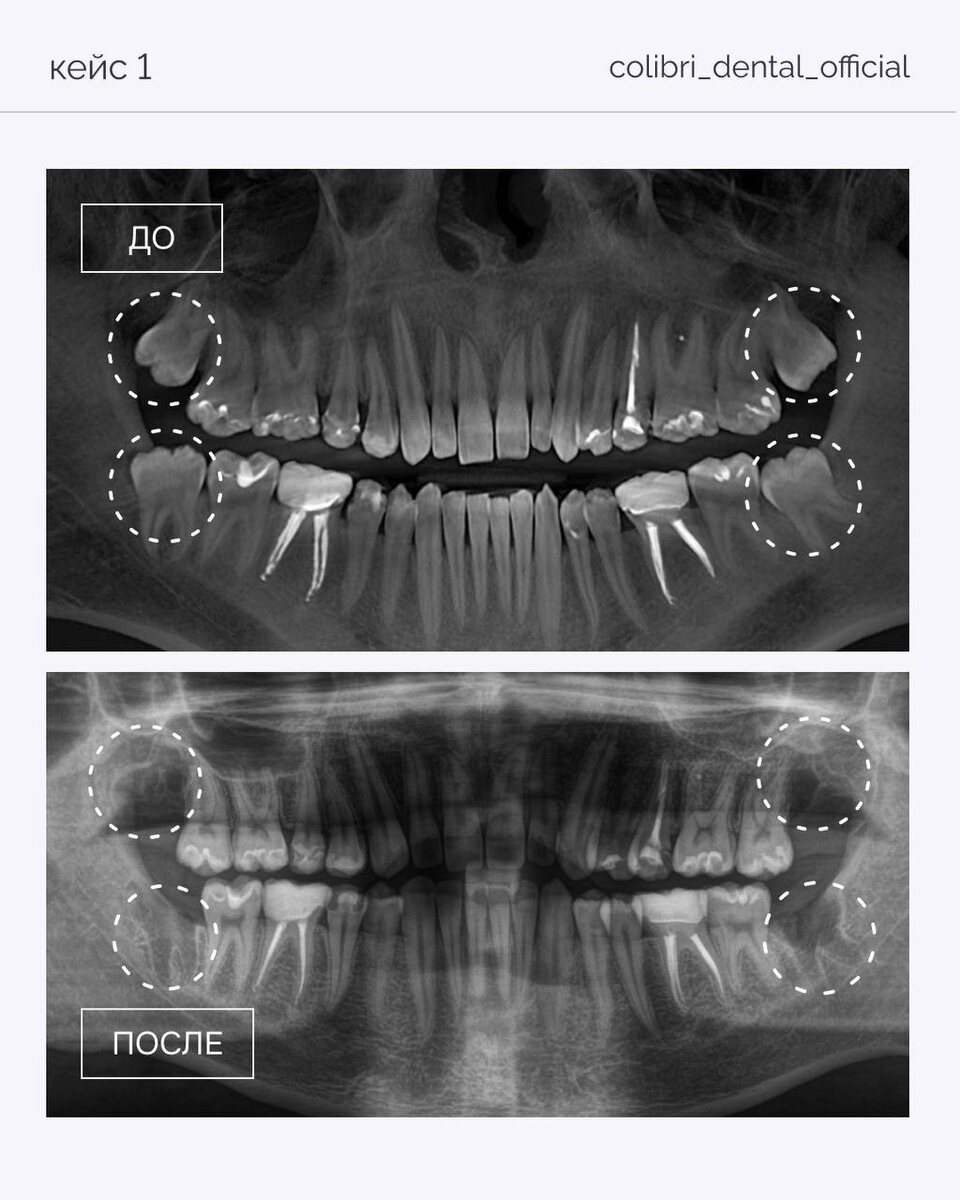

Зубы мудрости часто не дают выраженных симптомов

, но при этом могут: — смещать зубной ряд — вызывать давление и воспаление — осложнять ортодонтическое лечение Разобрали несколько кейсов в карточках. Важно: решение об удалении принимается только после диагностики (КЛКТ или панорама) и оценки положения зубов. Поможем оценить ситуацию и проконсультировать — для записи пишите в директ.

Разобрали несколько кейсов в карточках.

Важно: решение об удалении принимается только после диагностики (КЛКТ или панорама) и оценки положения зубов.